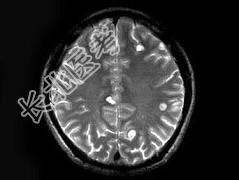

- 单项选择题男,29岁, 头痛不适半个月,MRI扫描如图, 最可能的诊断是 ( )

A、脑转移瘤

B、脑囊虫病

C、脑弓形虫病

D、脑脓肿

E、未见异常